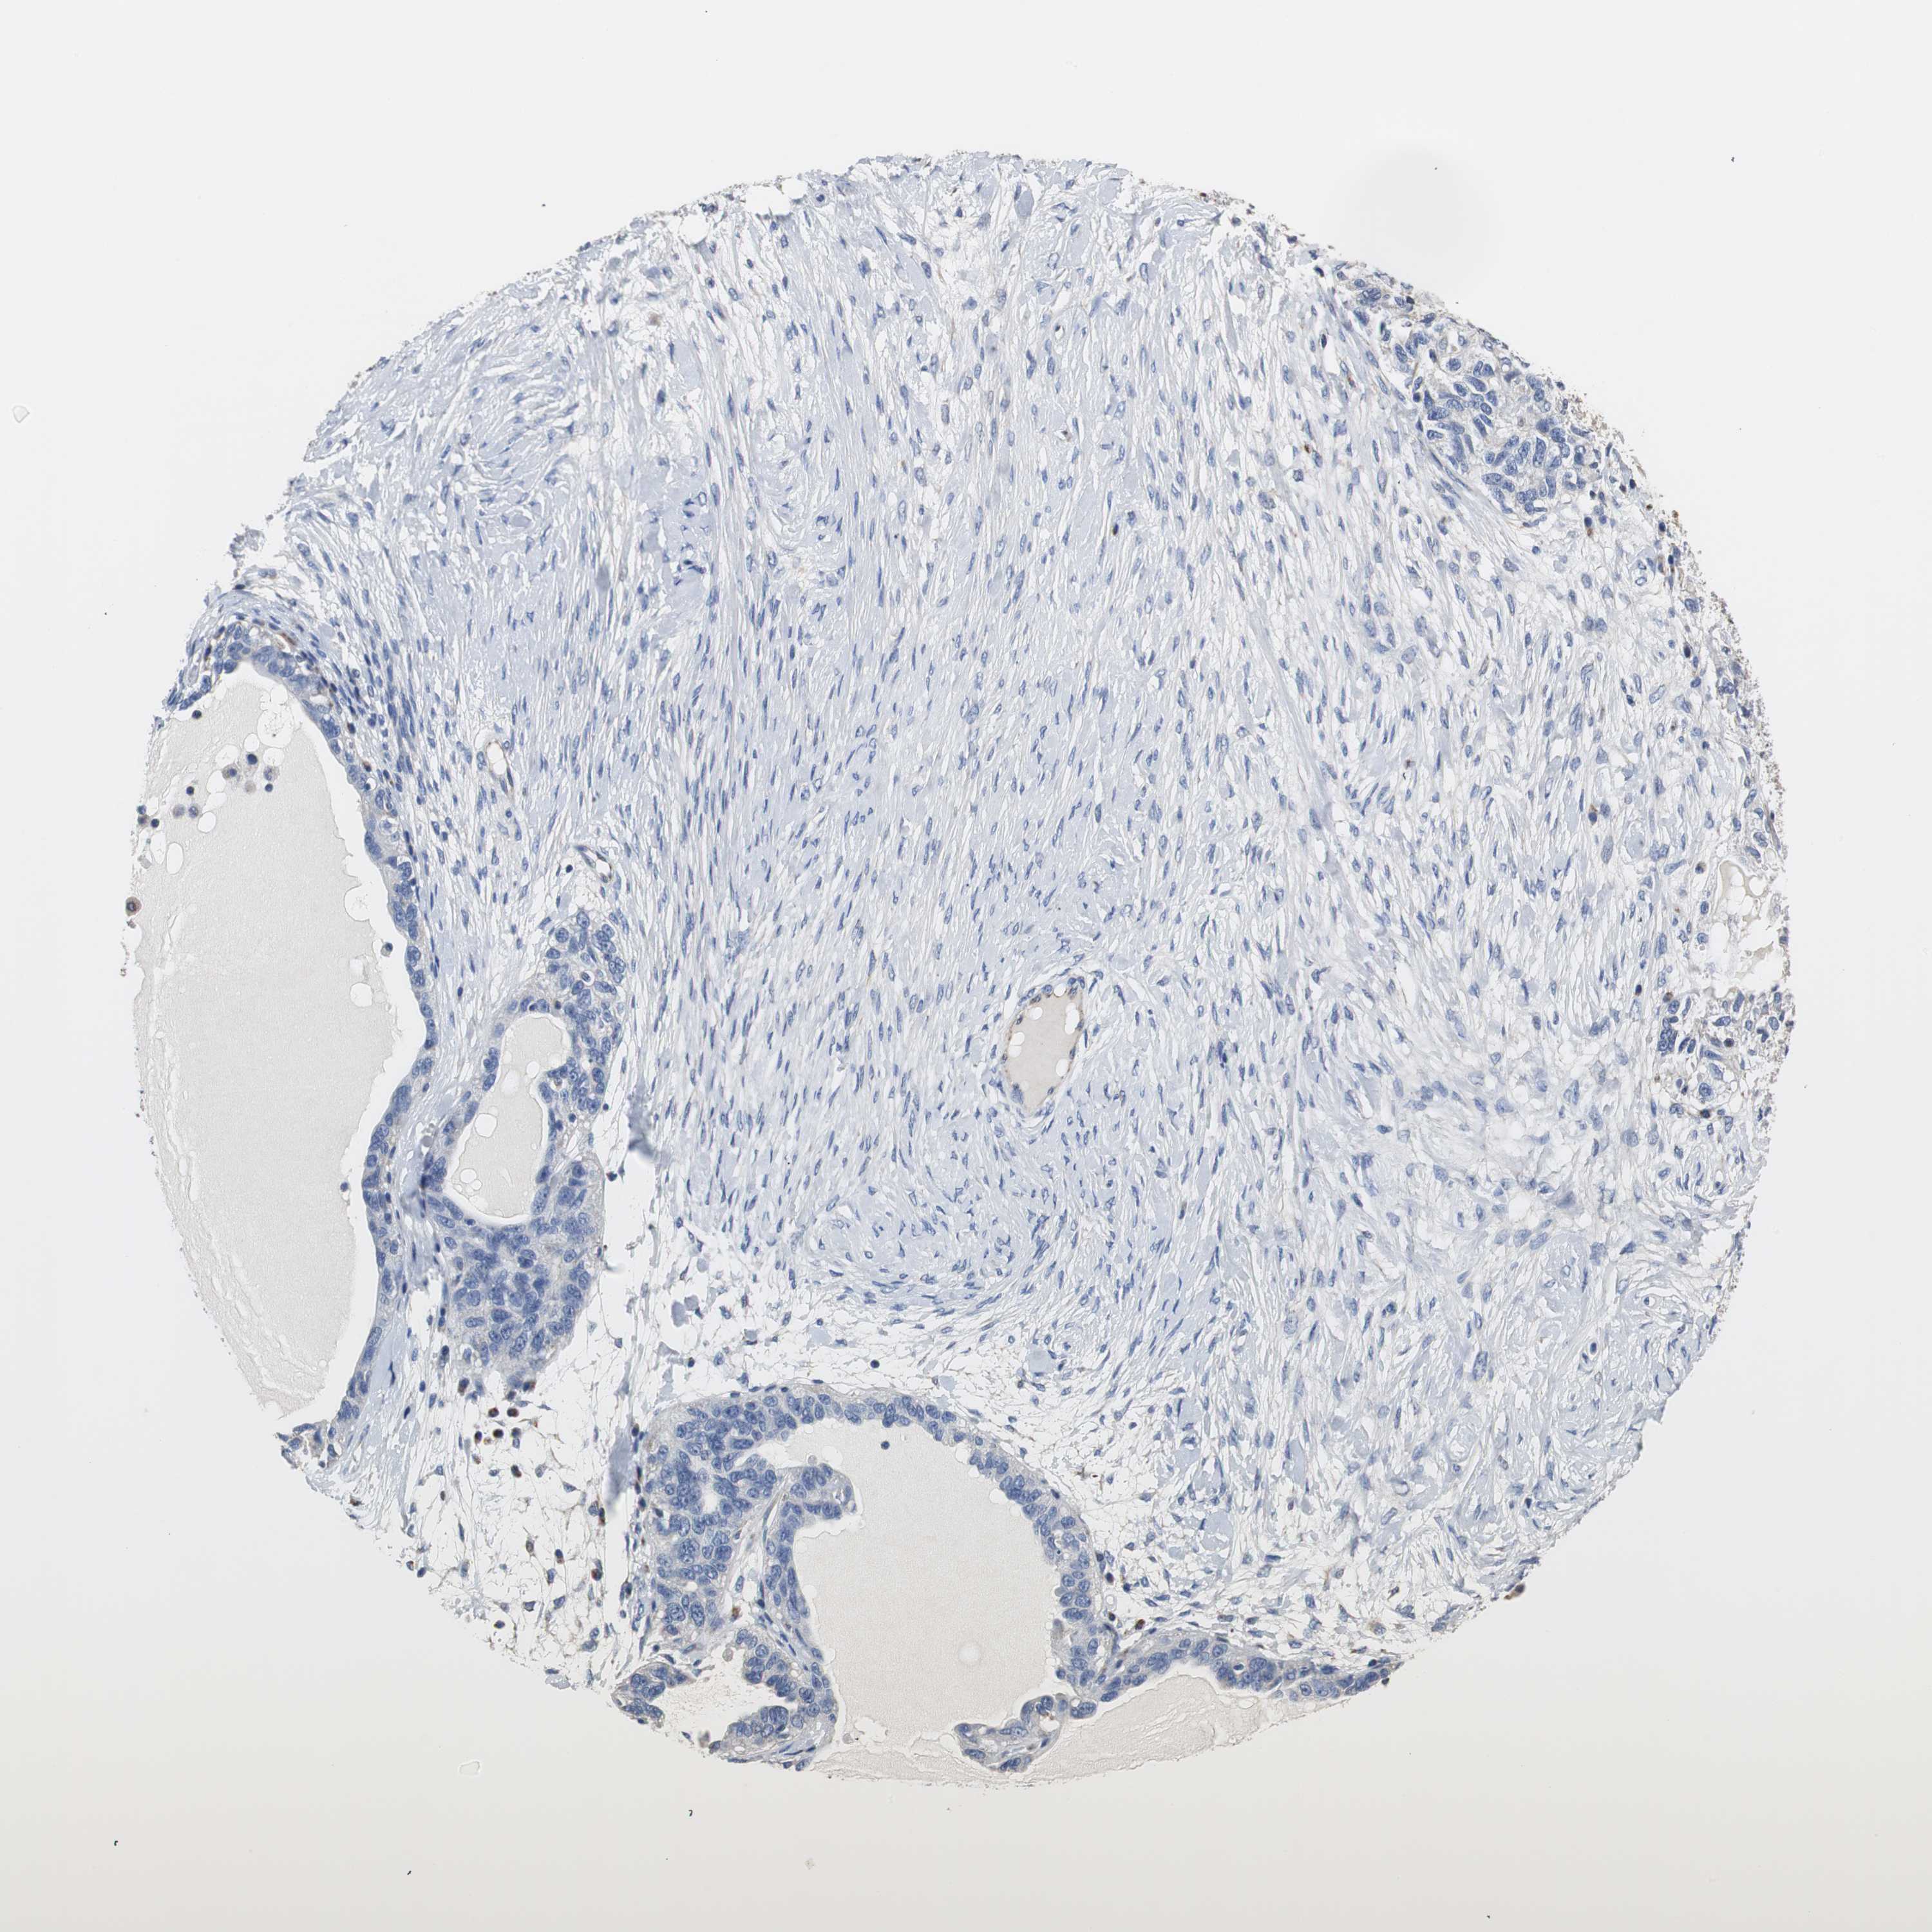

OVARIAN CANCER - Protein expressioni

A mouse-over function shows sample information and annotation data. Click on an image to view it in a full screen mode. Samples can be filtered based on level of antibody staining by selecting one or several of the following categories: high, medium, low and not detected. The assay and annotation is described here.

Note that samples used for immunohistochemistry by the Human Protein Atlas do not correspond to samples in the TCGA dataset.

Antibody stainingi

Antibody staining in the annotated cell types in the current human tissue is reported as not detected, low, medium, or high, based on conventional immunohistochemistry profiling in selected tissues. This score is based on the combination of the staining intensity and fraction of stained cells.

Each image is clickable and will lead to virtual microscopy that enables deeper exploration of all samples and also displays staining intensity scores, fraction scores and subcellular localization as well as patient and tissue information for each sample.

Antibody HPA006507

Staining

Low

Not detected

Cystadenocarcinoma, mucinous, NOS

Carcinoma, endometroid